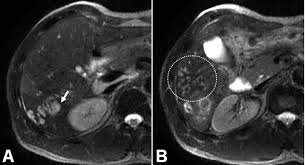

Loại tổn thương thứ hai mà chúng tôi hay gặp trong thời gian đầu của cấp tính là các khoảng trống như “khoang” hoặc có nhánh trông giống đường hầm, các dạng tổn thương này nhìn rõ nét hơn nếu so sánh và đối chiếu trên phim chụp CT Scanner hoặc MRI có bơm thuốc cản quang. Đây là những hình ảnh có ngoại vi ngoằn ngoèo, khúc khủy do quá trình sán di chuyển trong nhu mô gan và trong y văn ký sinh trùng cũng từng đề cập (F.Mansour Ghanaei và cs., 2006).

CT scanner có thể cho thấy hình ảnh đa khối tổn thương có kích thước 1-10 mm hoặc các đường hầm trong nhu mô gan-một mô hình lan rộng từ các đường hầm. CT scanner cũng có thể thấy sán trưởng thành trong đường mật hoặc túi mật. Các khảo sát bằng siêu âm và CT scanner đôi khi cũng nhầm lẫn với sỏi và khối thương tổn ác tính. Việc khảo sát cho nhiều lát cắt khác nhau và kích thước và độ dày mỏng khác nhau

Chụp MRI có thể thấy hình ảnh dạng u hạt trong nhu mô gan và có thể cung cấp các hình ảnh tương tự như trên CT scanner.

(i) Pha đầu tiên trên nhu mô gan, ấu trùng non xâm nhập vào nhu mô, tiếp sau đó là pha mật là đưa các ấu trùng vào trong đường mật. Siêu âm không đặc hiệu trong giai đoạn sớm. CT scanner có thể thấy vùng giảm âm dưới bao gan. MRI cũng có thể sử dụng để thiết lập vùng nhu mô bị ảnh hưởng, rõ ràng hơn trên CT scanner khi khảo sát tổn thương xuất huyết;